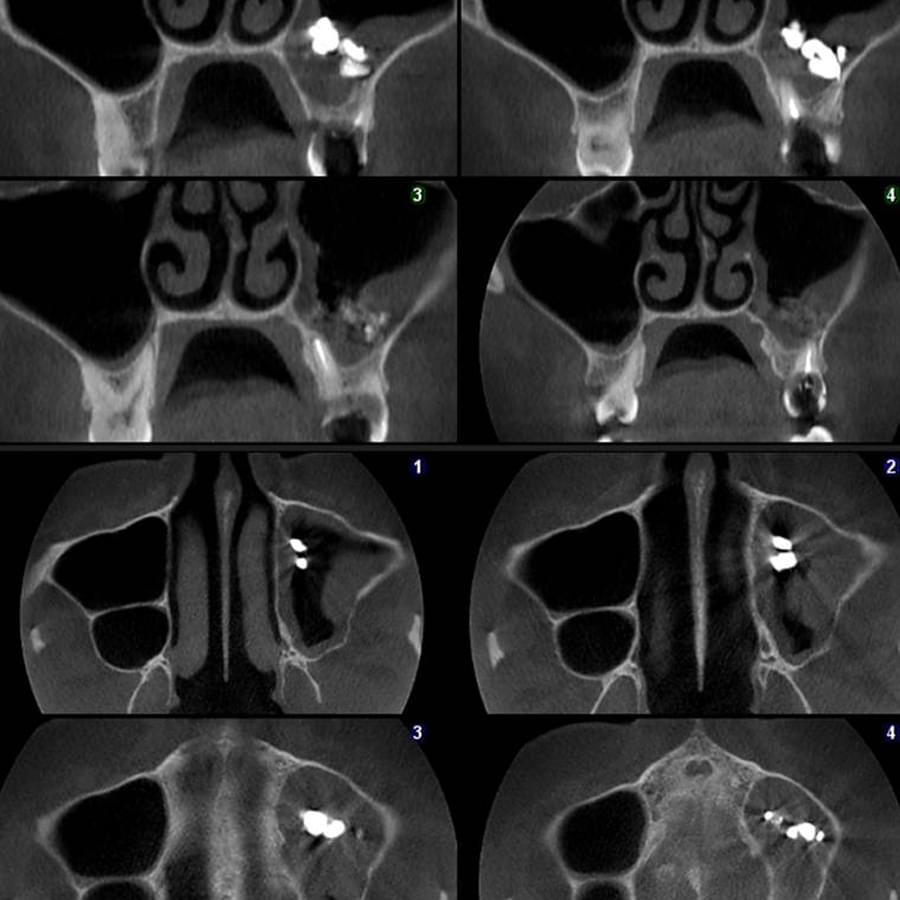

3D цефалометричний аналіз є сучасною технологією, яка дозволяє отримувати точніші,

комплексніші та надійніші дані про зубну та скелетну структуру. Ця технологія може стати

великим кроком в перед для ортодонтів, які хочуть забезпечити найкраще можливе лікування

своїх пацієнтів.

Основні переваги 3D цефалометричного аналізу:

Точність: 3D цефалометричний аналіз забезпечує точніше визначення розмірів та відстаней між

зубами та кістковими структурами.

Комплексність: ця технологія дозволяє отримувати детальні дані про різні структури, такі як

кістка та м'язи, що дозволяє ортодонтам докладніше досліджувати деякі патології та планувати

лікування.

Надійність: 3D цефалометричний аналіз дозволяє отримувати надійніші результати, оскільки

виключає можливість помилок, пов'язаних зі спотворенням або перекриттям зображень.